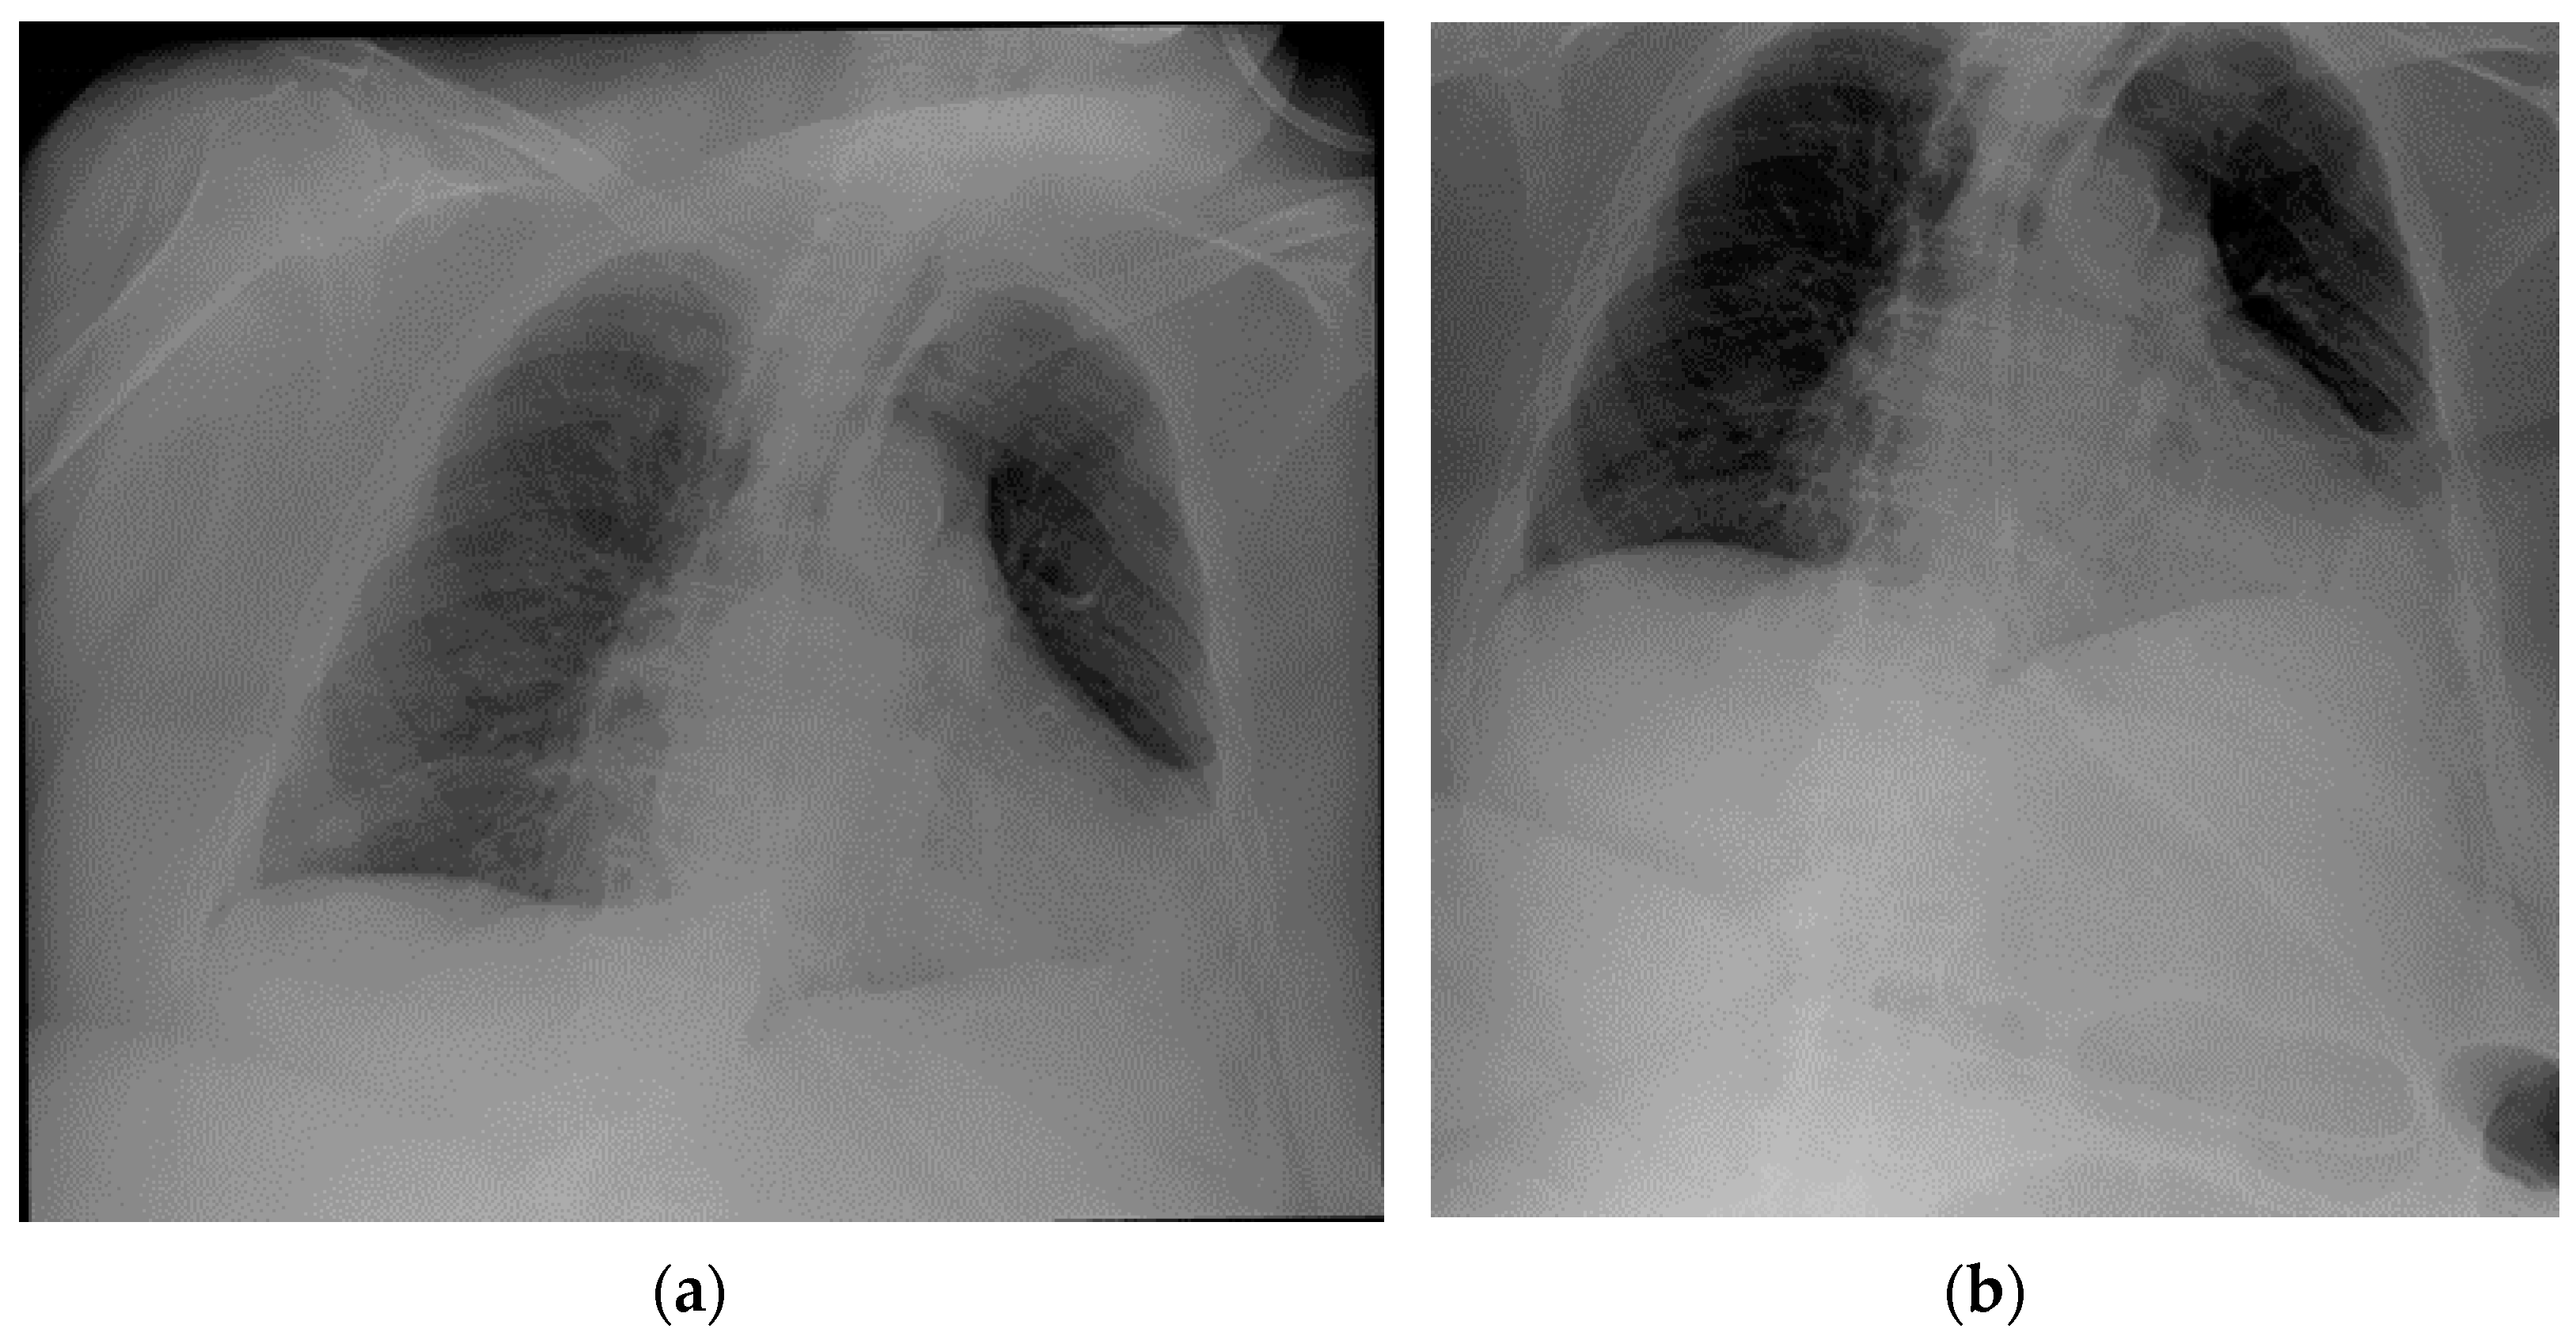

7. Chest Tubes

| Chest tubes | Kinking Extrapleural/intrafissural/intraparenchymal/misposition Mediastinum juxtaposition Diaphragmatic trespassing Mediastinal invasion (uncommon) |